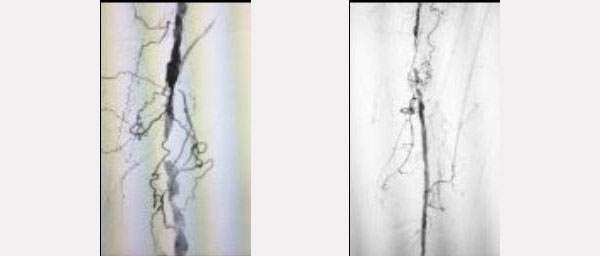

Paciente de 75 años.

Claudicación invalidante progresa a menos de 50 mtos a pesar del tratamiento medico.

Lesión severamente calcificada.

Preparación del vaso: